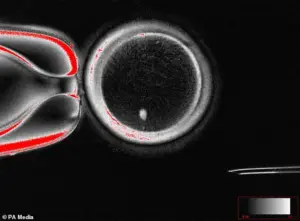

The process involves extracting the nucleus from a skin cell and inserting it into a donor egg that has had its nucleus removed—a technique that, while still experimental, has sparked both excitement and ethical debate among scientists and the public.

The implications of this research are profound.

For the first time, the possibility of creating eggs and sperm from somatic cells—without relying on traditional gametes—has moved from the realm of science fiction to the laboratory.

Dr.

Shoukhrat Mitalipov, a lead researcher on the project, described the breakthrough as a ‘major advance’ that could eventually allow two men to have a child without any genetic contribution from a woman.

However, the team emphasized that extensive safety testing is required before such procedures could be considered for clinical use.